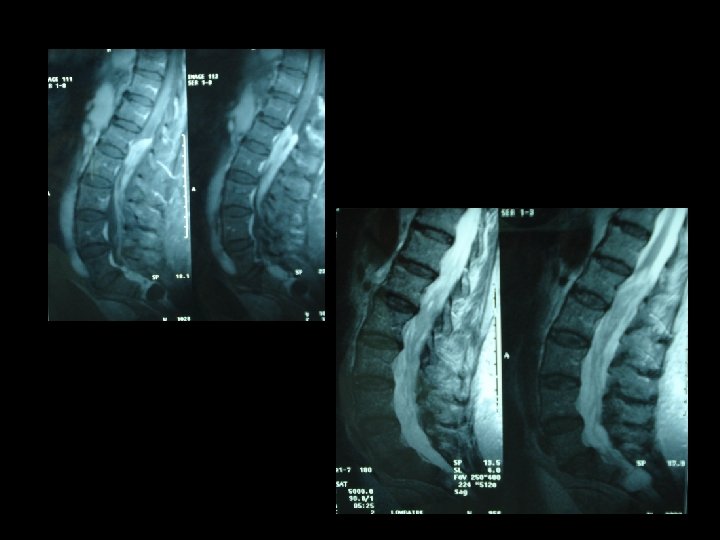

* Les examens biologiques misent en évidence une thrombopénie , une hypo albuminémie et une hypergammaglobulinémie modérée. Sérologie VIH était négative. * L’IRM lombaire pratiquée en séquence T 1, T 2 et avec injection du gadolinium montre un important épaississement des racines de la queue de cheval visible sur les coupes en séquence. T 2 qui se rehaussent intensément après injection du gadolinium.

* La présentation clinique n’est pas spécifique. * IRM médullaire : processus expansif étagé comprimant la moelle par endroit. * les lésions sont e hypo signal T 1, hyper signal T 2 et se rehaussant après injection du gadolinium. * l’IRM joue un rôle primordial dans le diagnostic des lymphomes à localisation médullaire.

* L'IRM vertébro-médullaire permet d'apprécier l'étendue de la tumeur et son extension vers les tissus mous et l'os permettant une orientation diagnostique et histologique. * Le diagnostic est histologique. * L'association radiothérapie chimiothérapie a prouvé son effet sur l'amélioration de la survie globale des patients.